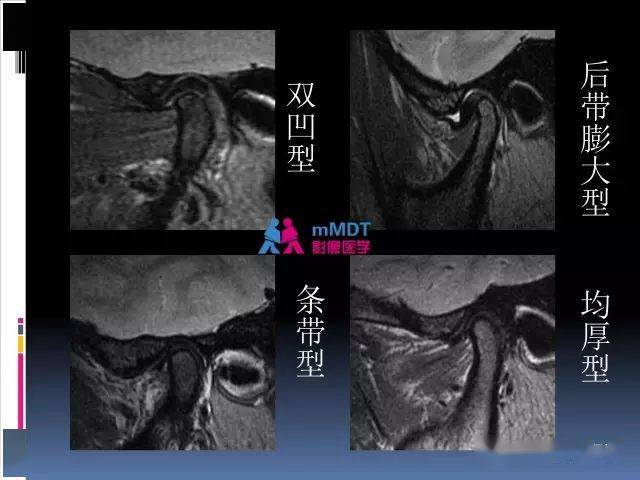

颞颌关节紊乱病的mri诊断_微信_影像_常读

颞下颌关节紊乱mri表现 | 影像天地

颞下颌关节的磁共振成像(检查技术与解剖部分)_影像_张静坤_腹股沟

颞下颌关节紊乱为什么要拍核磁共振? - 知乎